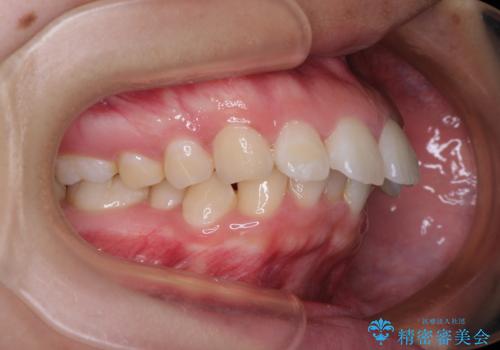

- 上顎前歯が飛び出していて唇がうまく閉じられないとのことで来院された患者様です。

くちばしのように前歯が突出していたため、口元を積極的に引っ込めるために、上下左右の小臼歯4本を抜歯することとしました。

また、上顎歯列が下顎に対して前方位に位置していたため、補助装置を用いて上顎歯列を後方に移動させ、より積極的に口元を下げるようにしました。